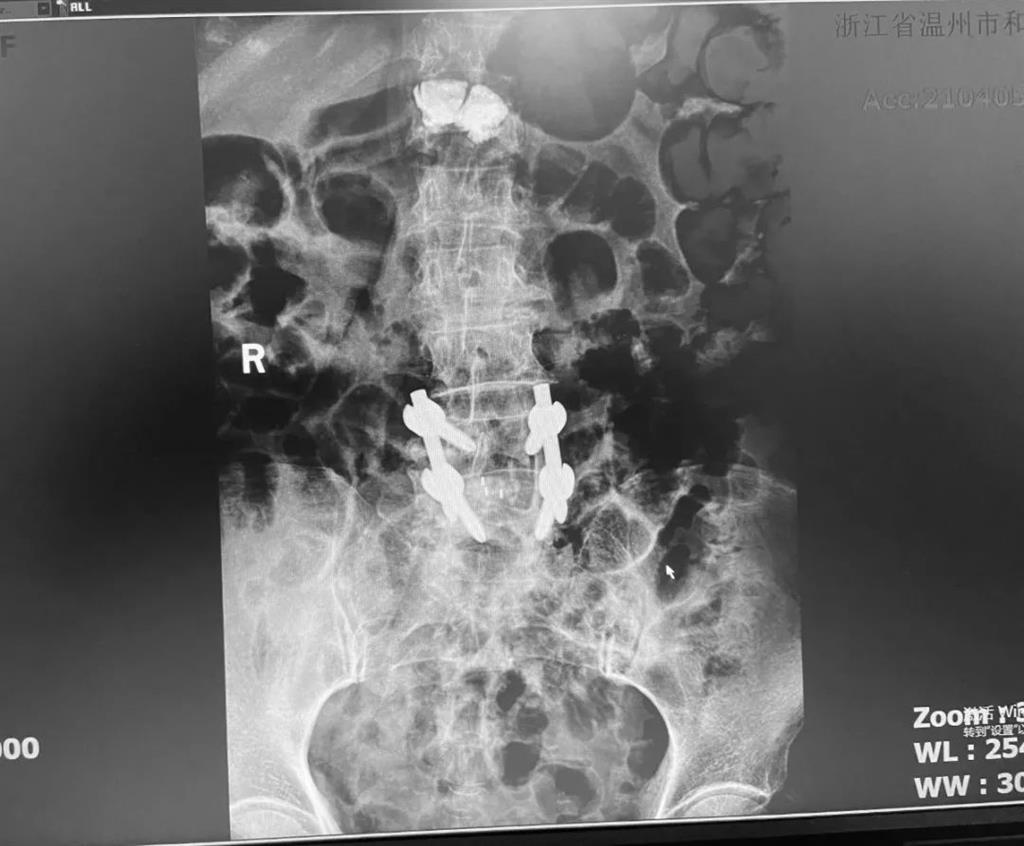

據(jù)了解,脊柱內(nèi)鏡下腰椎融合術(shù)只需要打幾個“鑰匙孔”即可完成。聽起來是不是很簡單?在脊柱內(nèi)鏡下,劉丹主任先后為患者進(jìn)行了椎管減壓、椎間盤摘除,再實施椎弓根螺釘放置、椎體植骨融合內(nèi)固定,一系列步驟有條不紊。

看似簡單的幾個步驟,但實際上很復(fù)雜,需要主刀醫(yī)生有豐富的手術(shù)經(jīng)驗和細(xì)致耐心的操作。